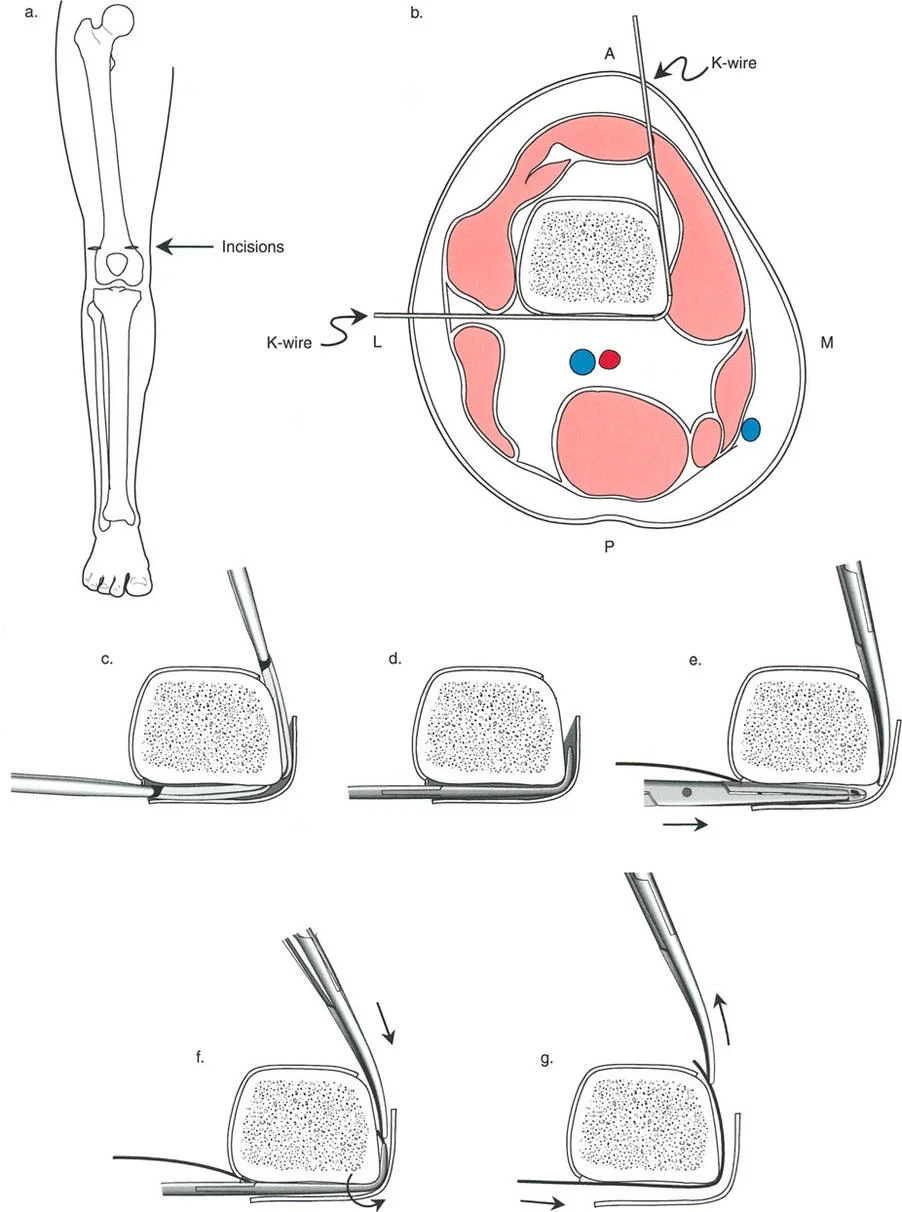

قيود الأسلاك والدبابيس في القاعدة 2

لتحقيق هذه الترجمة الضرورية والمقصودة بسلاسة باستخدام إطار دائري كامل الأسلاك، يلزم استخدام أسلاك الزيتون المعاكسة (counter-opposed olive wires). تعمل أسلاك الزيتون كقوى سحب ديناميكية، تسحب قطعة العظم على طول الحلقة أثناء فتح المفصلات. بدون أسلاك الزيتون، سيبقى العظم ثابتًا بينما تتحرك الحلقة عبر الأنسجة الرخوة، مما يسبب نخرًا شديدًا في الجلد.

على العكس من ذلك، إذا تم استخدام دبابيس نصفية (مسامير شانز)، فإنها تقيد العظم بطبيعتها بالحلقة. نظرًا لأن الدبابيس النصفية هي أذرع صلبة (مثبتة من طرف واحد بالحلقة ومغروسة في العظم من الطرف الآخر)، فإنها لا تسمح للعظم بالانزلاق على طول محور السلك. هذا يجعل أسلاك الزيتون غير ضرورية للترجمة في منشآت الدبابيس النصفية، ولكنه يتطلب من الجراح التأكد من أن الدبابيس النصفية قوية بما يكفي (عادةً دبابيس بقطر 5 مم أو 6 مم مطلية بهيدروكسي أباتيت) لتحمل لحظات الانحناء الناتجة عن الترجمة.

نصائح جراحية للمنشآت القريبة من المفصل

| تقابل الأسلاك | استخدم ما لا يقل عن سلكين زيتون متقابلين لكل قطعة إذا كنت تتجنب الدبابيس النصفية. | الأسلاك الزيتون الفردية ستسبب قصًا ودورانًا غير مرغوب فيه حول محور السلك. |